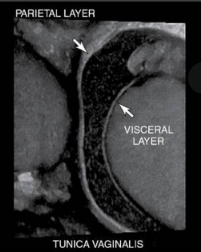

the testis are covered by the...

tunica albuginea

what lines the inner surface of the scrotum

tunica vaginalis

what are the layers of tunica vaginalis

parietal- creates the scrotal wall

visceral- surrounds testis and epi

where do hydroceles form

in space between parietal and visceral layers tunica vaginalis